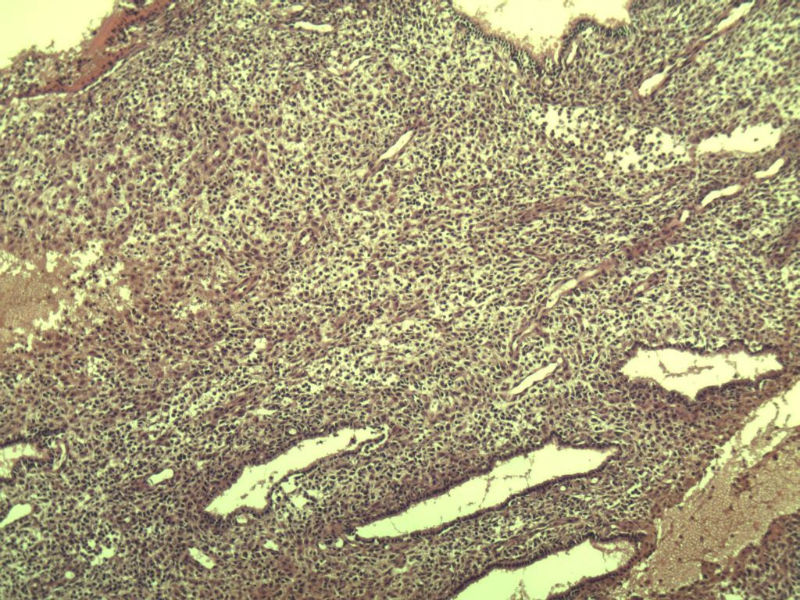

这是另外一个 40岁 经期延长 流血量增多 半年 这是蜕膜样变吧 有什么意义吗? 要报告不?